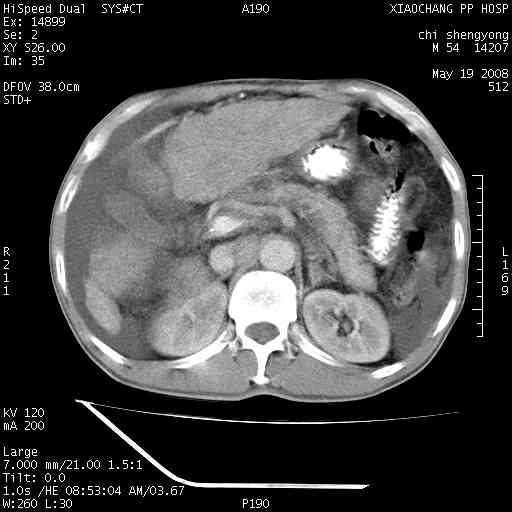

以下是引用zjzjr在2008-5-21 10:52:00的发言:[br]肝左叶巨块型肝癌伴门静脉左支瘤栓形成.肝硬化、腹水,胃底静脉曲张,脾术后改变。

以下是引用随光逐影在2008-5-21 16:20:00的发言:[br]1)肝左叶肝癌伴门静脉左支瘤栓形成,腹膜后淋巴结转移。2)肝硬化、腹水、胃底静脉曲张。3)胆囊炎。4)脾脏缺如,为切除术后所致。